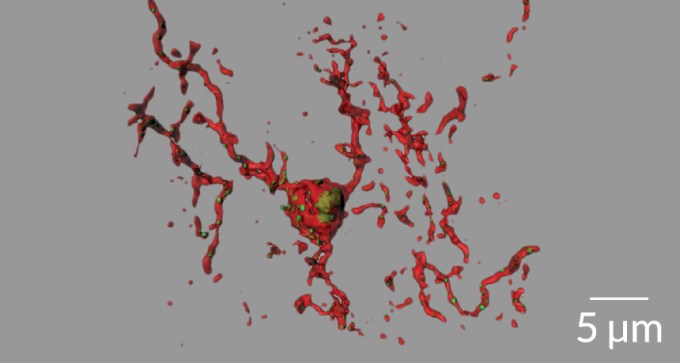

Nerve cell links severed in early stages of Alzheimer’s

Nerve cell connections may be trimmed too much in early stages of Alzheimer’s.